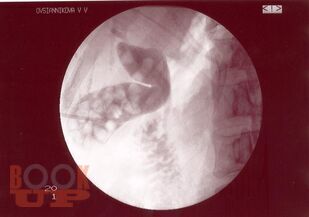

В учебном пособии представлены современные методы лечения ЖКБ. Рассмотрены как хирургические, так и консервативные способы. Показаны их преимущества и недостатки. Также отражены распространенность, патогенез, клиника и диагностика данного заболевания. Пособие предназначено для врачей-терапевтов, врачей общей практики, гастроэнтерологов, врачей скорой помощи, абдоминальных хирургов, интернов, ординаторов.